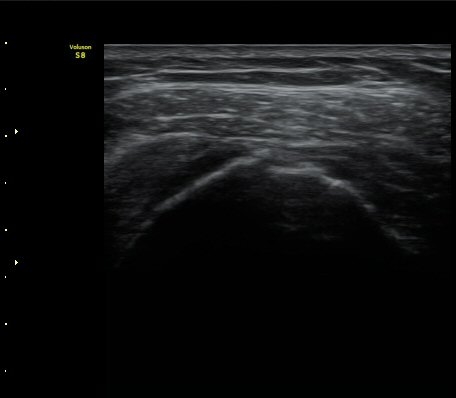

±Ø»ó°Ç Ⱦ´Ü¸é°Ë»ç»ó »ó¿Ï°ñµÎ¸¦ µ¤°í ÀÖ¾î¾ßÇÒ ±Ø»ó°ÇÀÌ º¸ÀÌÁö ¾Ê°í Á¡¾×³¶ÀÌ ÆíÆòÇϰÔ

³»·Á ¾É¾Æ º¸ÀδÙ(±×¸² 3).